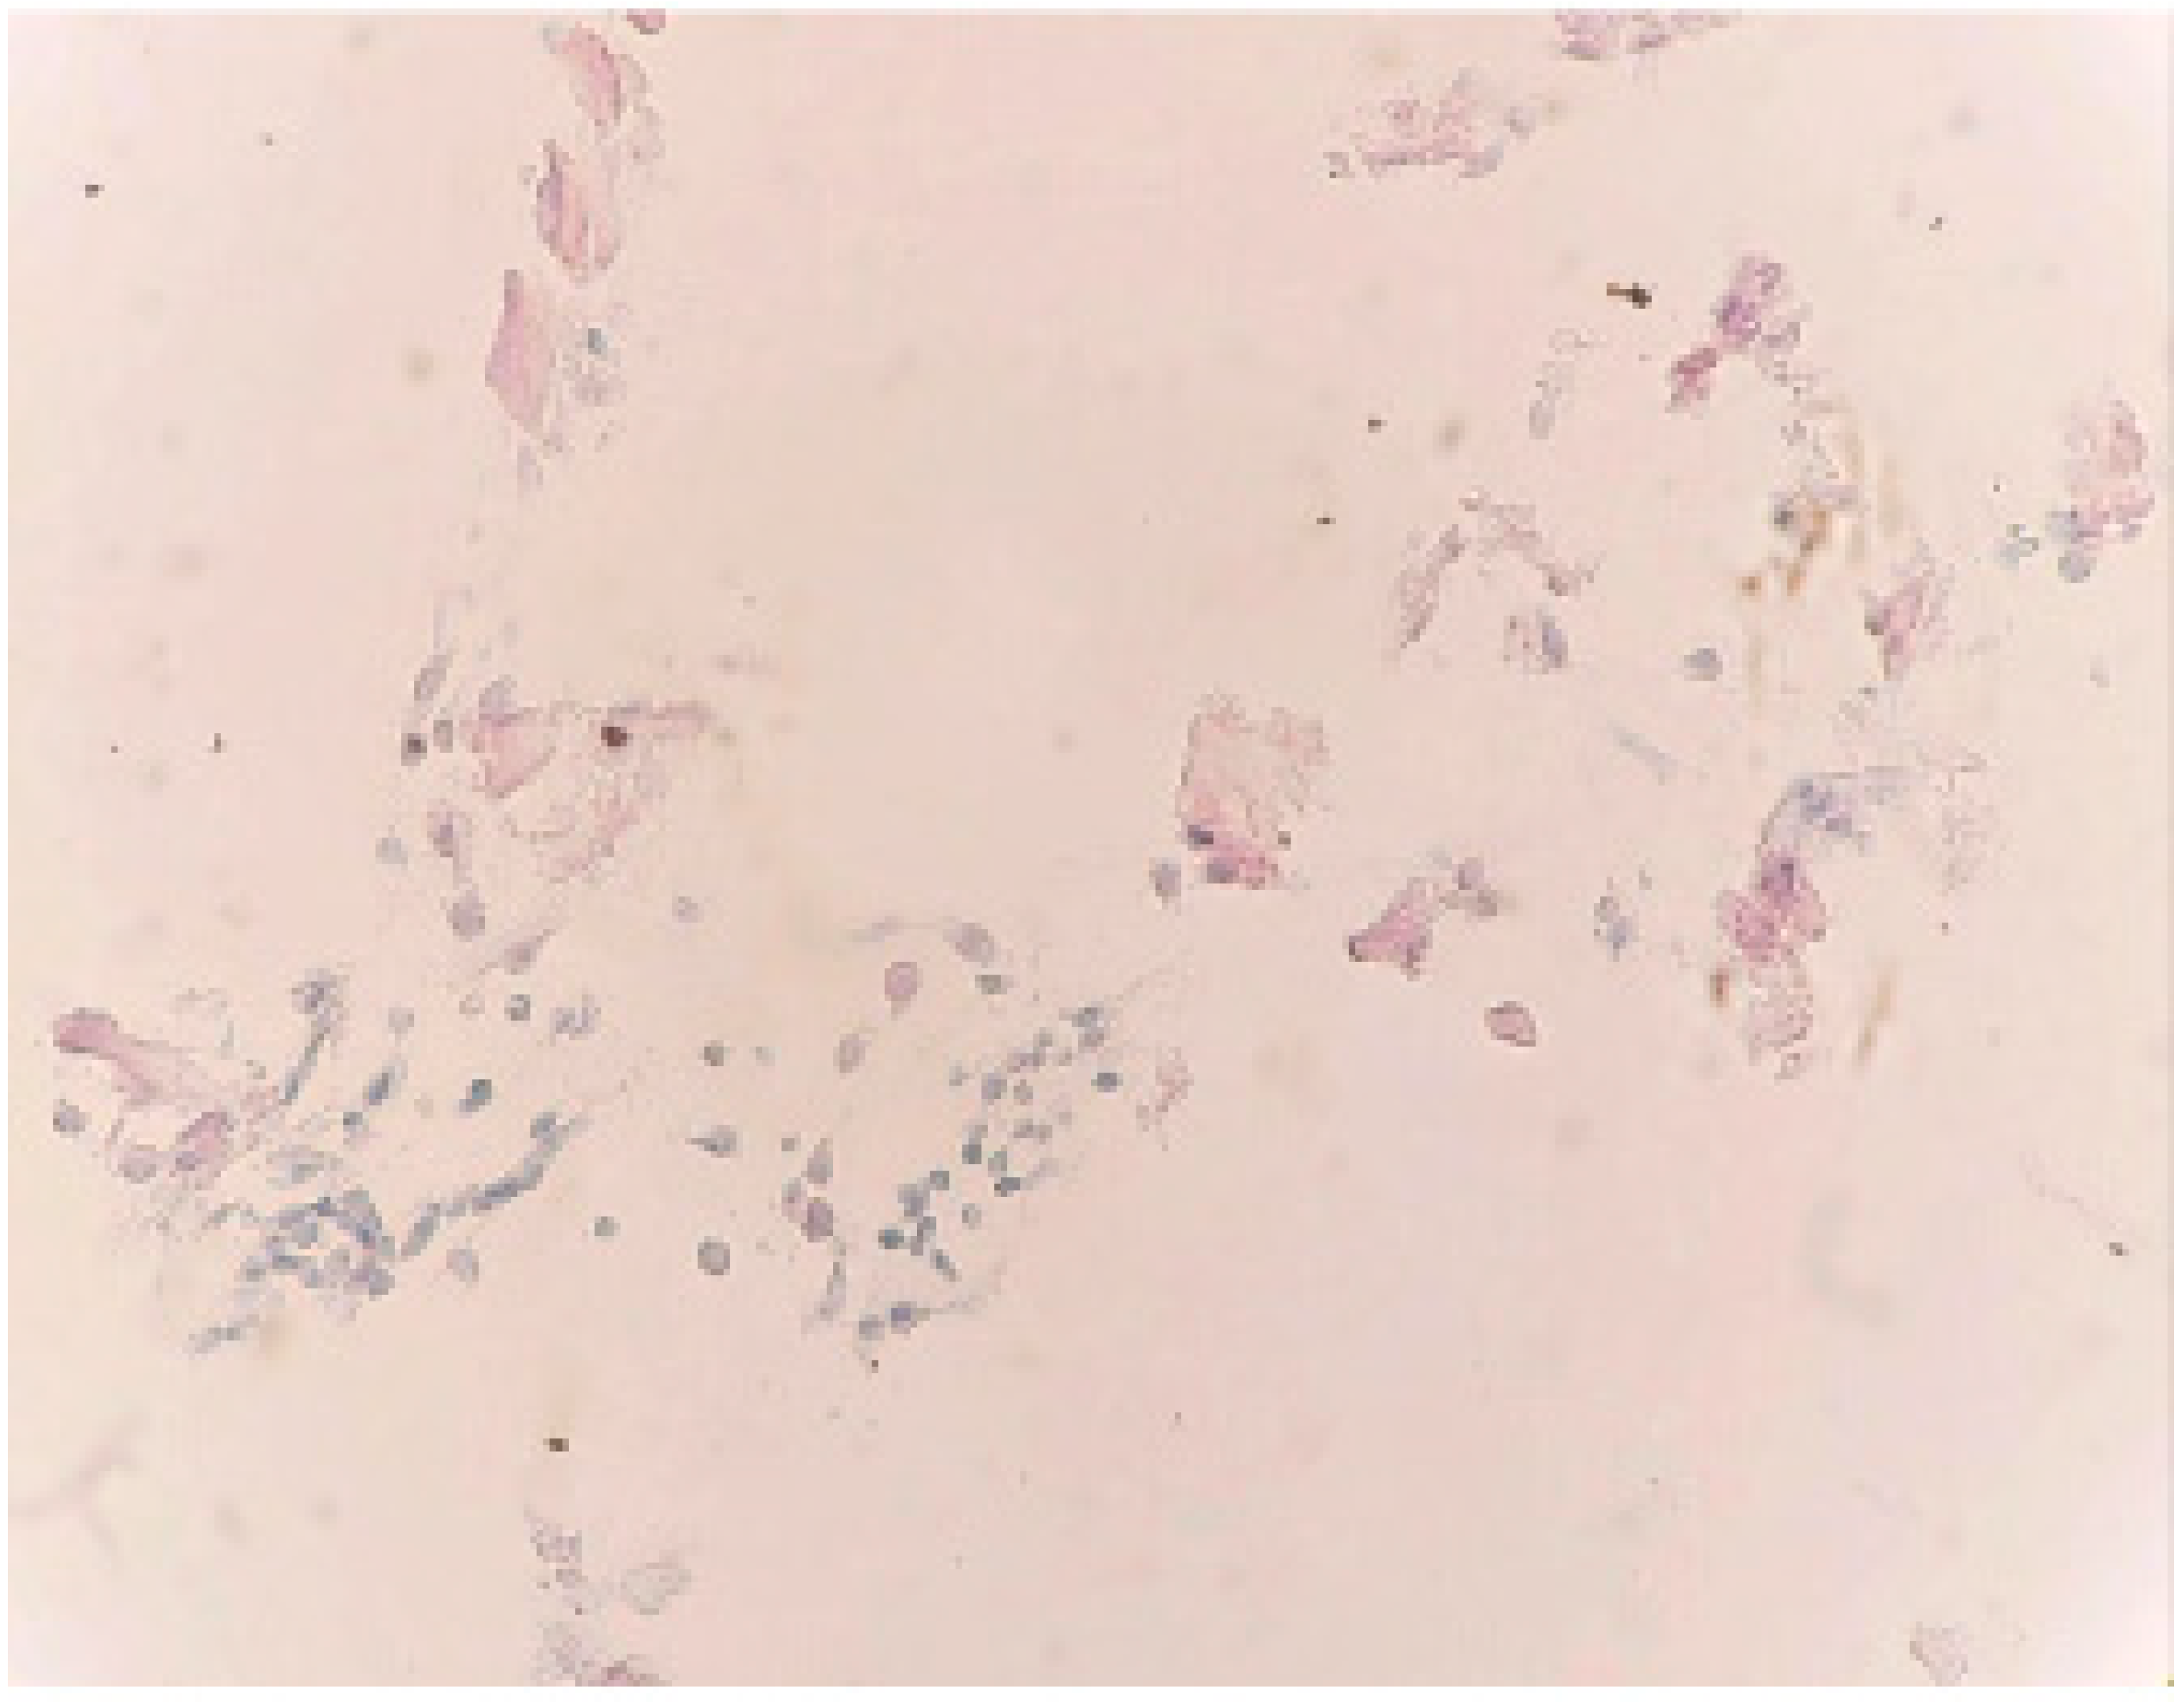

Case Report